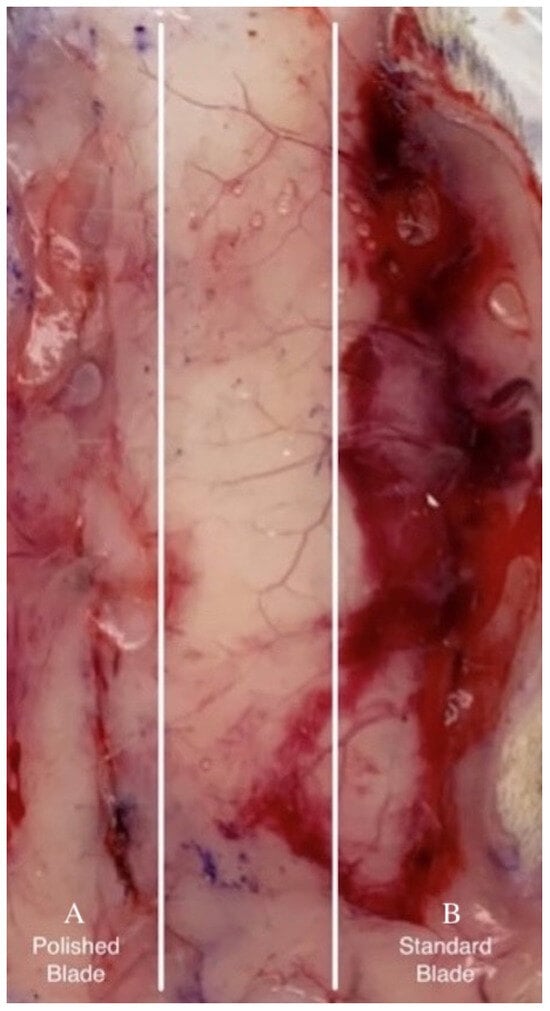

Figure 3.

Bleeding under tissue excised 1 day post-surgery: incisions made by EB (A) and SB (B).

Morphometric wound analysis reveals site-specific differences in healing for the two types of incisions. While not quantified, in tissue samples collected 1 day after surgical incision, subcutaneous blood staining was frequently observed in incisions made with the SB and less frequently with the EB (Figure 3). Monitoring blood staining was not part of the experimental plan. Within 3 days after skin incisions, the majority of wounds produced by SB did not achieve closure (Figure 4). In contrast, approximately 90% of incisions made by EB exhibited adherence in this same period. The results show that the wound treated with SB did not close completely on the third day; however, the one treated with EB did. By day 7, all wounds achieved closure. After 2 months, all incisions were completely healed, and the dorsal skin softness and elasticity were qualitatively judged to be normal.